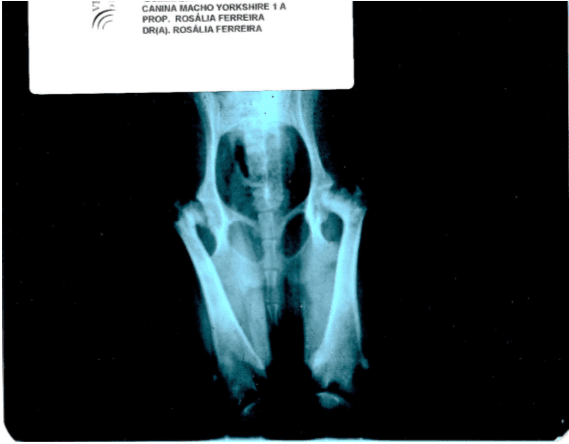

Canino macho, raça Yorshire, 1 ano de idade, pesando 2 kg. Começou a apresentar impotência funcional do membro posterior direito. O animal não conseguia apoiar o membro. Foi realizada radiografia de articulação coxofemoral (02/04/2011), onde se observou conforme laudo “incongruência articular bilateral coxofemoral (mais evidente em acetábulo direito) alteração morfológica de cabeças femorais e área radiotransparente em cabeça femoral direita e em colo femoral esquerdo (osteólise). Imagens sugestivas de doença de Legg-Calvé-Perthes bilateral[2]”. Três dias após a radiografia (05/04/2011) foi iniciado o tratamento com o produto [3]Homeopet Displasia® (Hekla lava 10-400, Symphytum officinale 10-40, Calcium fluoricum 10-60 , Hekla lava 10-40), o protocolo seguido foi de 1 borrifada via oral 5 vezes ao dia. A melhora foi progressiva e após 1 mês de tratamento o animal já apoiava o membro posterior direito andando normalmente.

Radiografia, imagem compatível com Necrose Asséptica da Cabeça do Fêmur ou doença de Legg-Clavé-Perthes.

Laudo emitido pelo centro de diagnostico por imagem. Radiografia sugestiva de doença de Legg-Clavé-Perthes.